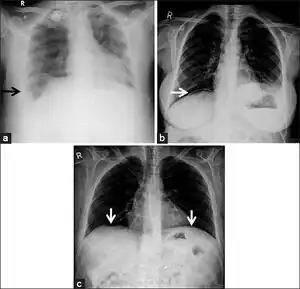

Differential diagnosis

Pseudopneumoperitoneum a) Chest radiograph of Chilaiditi syndrome showing large bowel loops arrow under the diaphragm b) linear atelectasis c) loculated air beneath the diaphragms following colonoscopy[5]

As differential diagnoses, a subphrenic abscess, bowel interposed between diaphragm and liver (Chilaiditi syndrome), and linear atelectasis at the base of the lungs can simulate free air under the diaphragm on a chest X-ray.